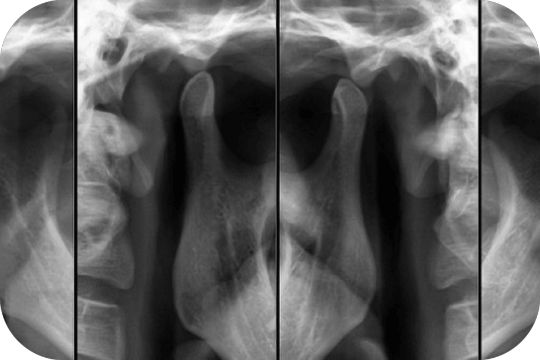

ATM